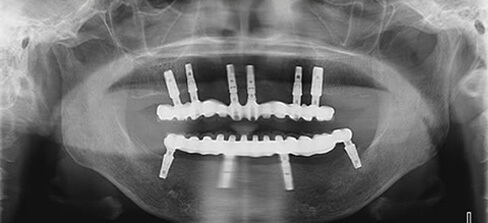

インプラント治療例その2(重度歯周病患者様、上顎に6本下顎に4本インプラント埋入、60歳代女性)

残念ながらここまで歯周病が広範囲かつ重度に進行してしまうと全て抜歯→総義歯が一般的な治療方針となりますが、患者様の強いご希望により必要最小限の本数を用いたインプラント治療によって、固定性補綴物による咀嚼回復が可能となりました。

暫間義歯を装着しCT撮影・診断の後インプラント埋入位置を決定、その位置へ正確に埋入するため作製されたサージカルガイドを用いて手術を行います。

術前レントゲン写真

術後レントゲン写真

| 治療内容 | インプラント治療(重度歯周病患者様、上顎に6本下顎に4本インプラント埋入) |